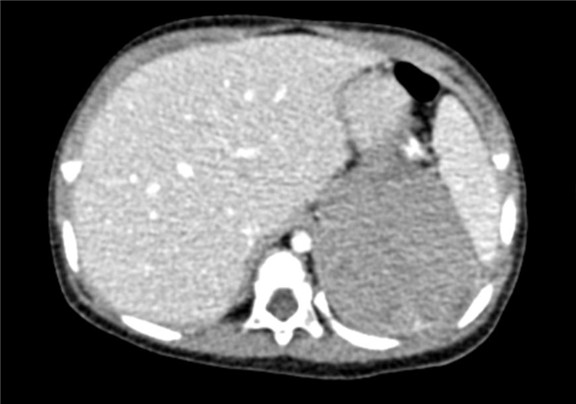

2017-02-03 上腹部CT平扫:左肾区巨大占位,肾母细胞瘤?建议CT增强检查;右肾结石可能性大;腹腔积液。

将0.625mm双源薄层CT资料的静脉期和动脉期Dicom格式文件导入海信CAS系统。

通过调节窗宽窗位调整CT序号,对肿瘤,肝实质,胆囊,下腔静脉,肿瘤,肝动脉、门静脉及肝静脉等进行三维重建;系统自动计算肿瘤体积和肝脏体积。

术前CT检查:

动脉期

静脉期